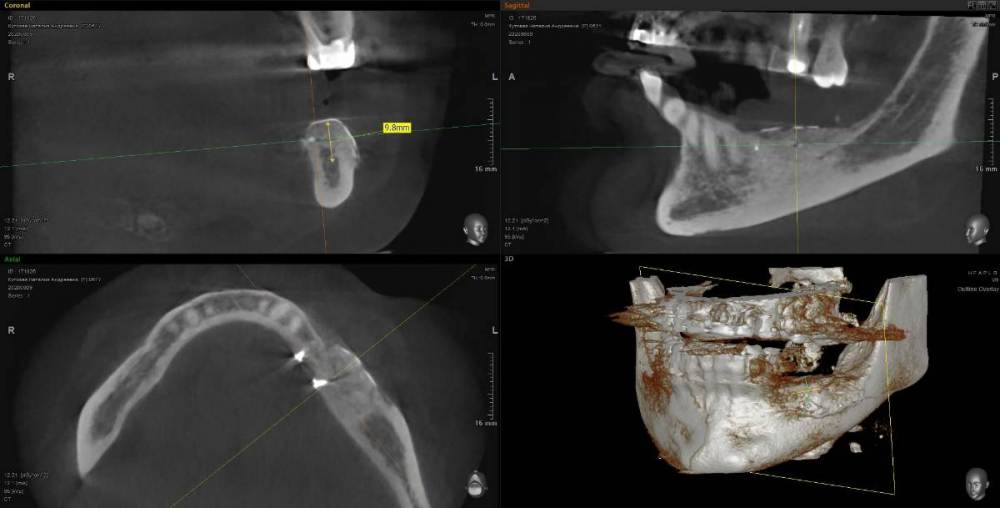

Kostoprav Опубликовано 11 мая, 2021 Поделиться Опубликовано 11 мая, 2021 (изменено) 70%ауто+30% ксено, мембрана цитофлекс, винты самосверлящие после пластики до установки имплантов прошло 8 мес. Изменено 11 мая, 2021 пользователем Kostoprav 3 6 Ссылка на комментарий

Карен Аванесов Опубликовано 12 мая, 2021 Поделиться Опубликовано 12 мая, 2021 20 часов назад, Kostoprav сказал: 70%ауто+30% ксено, мембрана цитофлекс, винты самосверлящие после пластики до установки имплантов прошло 8 мес. Замечательно! 1 Ссылка на комментарий